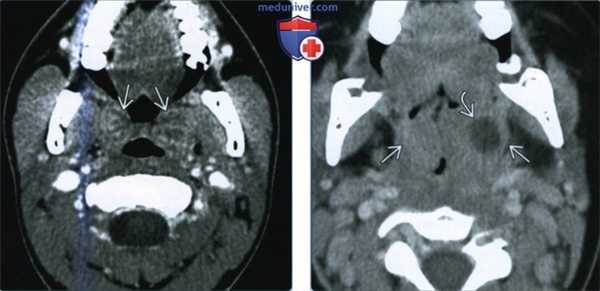

(Слева) При КТ с КУ в аксиальной проекции определяется большой МА с содержимым пониженной плотности. Распространения в окологлоточное пространство за пределы капсулы миндалины нет. Левая миндалина увеличена и накапливает контраст, но признаков абсцедирования нет. Обратите внимание на сопутствующий выпот в заглоточном пространстве.

(Справа) При КТ с КУ в аксиальной проекции определяются миндаликовые абсцессы с обеих сторон, левый по размерам больше правого. Абсцессы сдавливают оба окологлоточных пространства, но распространения воспалительного процесса на окружающие структуры нет. Просвет дыхательных путей сужен и имеет щелевидную форму.